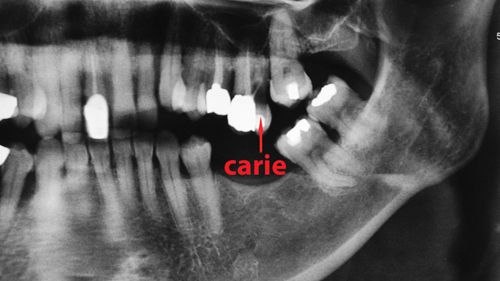

La perte d’une dent peut avoir des conséquences importantes sur les dents adjacentes. En effet, ces dernières peuvent basculer et se déplacer, entraînant des caries et des problèmes de gencives. Pour éviter cela, il est recommandé de remplacer la dent manquante par un bridge ou une couronne sur implant afin de stabiliser les dents et de prévenir les mouvements dentaires indésirables.